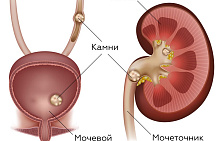

Одним із найнеприємніших хронічних захворювань є сечокам'яна хвороба. Вона характеризується появою в сечових шляхах та нирках кристалів-каменів, які з'являються внаслідок кристалізації компонентів сечі. Як показує статистика, симптоми сечокам'яної хвороби виявляються більш ніж у 30% випадків захворювань, пов'язаних із урологією, поступаючись лише інфекційно-запальним процесам.